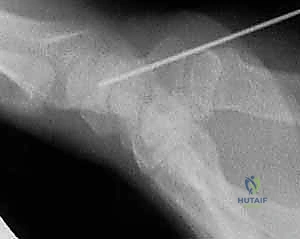

### Nondisplaced Fracture of the Scaphoid Waist or Proximal Pole Position the wrist to obtain a PA view of the wrist. Under fluoroscopic guidance, gently pronate the wrist until the scaphoid appears as an oblong cylinder, indicating that the proximal and distal poles are aligned. Flex the wrist about 45 degrees until the cylinder rotates into the plane of imaging, forming a “ring” sign. The center of the ring indicates the central axis of the scaphoid ( TECH FIG 1). Using a 14-gauge angiocatheter as a guide for wire insertion, place the tip of a 0.045-inch guidewire through the catheter and onto the proximal pole of the scaphoid, at the center of the scaphoid ring. Confirm correct positioning with fluoroscopy. 24, 25 Insert the guidewire down the central axis of the scaphoid using a wire driver. Keep the wrist flexed to avoid bending the wire. Insert the guidewire through the trapezium and advance it until the proximal tip of the guidewire clears the radiocarpal joint such that the wrist can be extended for arthroscopic examination.

Confirm correct wire position with fluoroscopy.

TECH FIG 1 • The scaphoid ring sign indicates the central axis of the scaphoid, which is critical for accurate insertion of the cannulated compression screw. A,B. The wrist is positioned in flexion and pronation until the scaphoid appears as a ring (

arrow

) on fluoroscopic imaging. A 0.045-inch guidewire is inserted through the center of the ring.